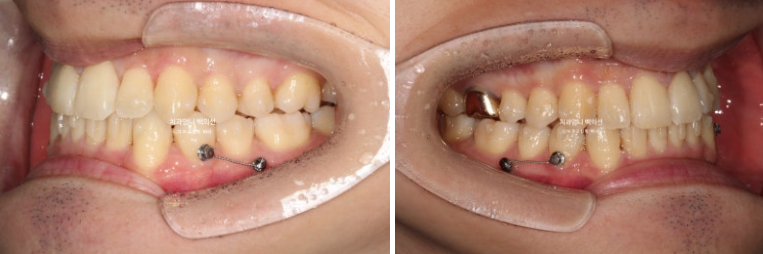

22.10

구치부 교합은 3급이며 앞니 뻗침이 보입니다.

입술이 돌출된 건 아니지만 말하거나 웃을때 앞니가 뻗쳐있어 돌출감을 느끼는 상태입니다.

24.09

앞니 중심선 불일치가 많이 좋아졌으나 아직 완벽히 맞지는 않습니다.

어금니 교합도 교합관계 자체는 1급으로 좋아졌으나 위아래 틈이 보입니다.